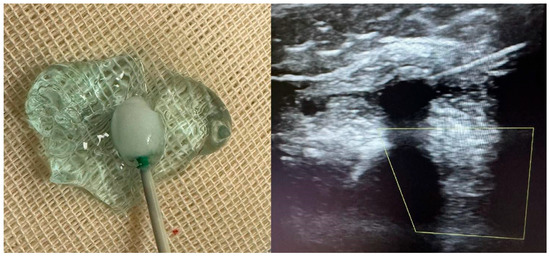

Exploratory Use of Proximal Cryoneurolysis and Distal Botulinum Toxin Type A for Upper-Limb Spasticity: A Case Report with Scoping Review

by Di Lorenzo Luigi, De Meo Bruno, Forte Alfonso Maria, Forte Francesco, Palmieri Vincenzo, Pirraglia Nicola and D’Avanzo Carmine

Toxins 2026, 18(2), 66; https://doi.org/10.3390/toxins18020066 - 27 Jan 2026

Background: Upper-limb spasticity involving the shoulder girdle and elbow flexors often impairs functional hand use, and although Botulinum toxin type A (BoNT-A) is a first-line therapy, severe proximal synergies may persist while higher doses risk distal weakness. Methods: We report a case of [...] Read more.

Background: Upper-limb spasticity involving the shoulder girdle and elbow flexors often impairs functional hand use, and although Botulinum toxin type A (BoNT-A) is a first-line therapy, severe proximal synergies may persist while higher doses risk distal weakness. Methods: We report a case of a 47-year-old woman with neurodegenerative tetraparesis and marked shoulder and elbow flexor spasticity treated with bilateral percutaneous cryoneurolysis of the lateral pectoral, thoracodorsal, and musculocutaneous nerves, followed by distal BoNT-A injections, and we conducted a scoping review following Arksey and O’Malley, Levac, and PRISMA-ScR methods to contextualize the current evidence. Results: At one-month follow-up, the patient showed a reduction in MAS from 4 to 1–2, complete resolution of pain, improved passive shoulder abduction and elevation, preserved distal dexterity, and high satisfaction with no adverse events. The scoping review identified consistent MAS and range-of-motion improvements across multiple case reports and small series involving similar proximal nerve targets. Conclusions: The combined proximal cryoneurolysis–distal BoNT-A approach appears to be a feasible dual-modulation strategy for complex upper-limb spasticity when the preservation of hand function is essential, and the emerging literature supports its further investigation. Full article

Show Figures

Figure 1